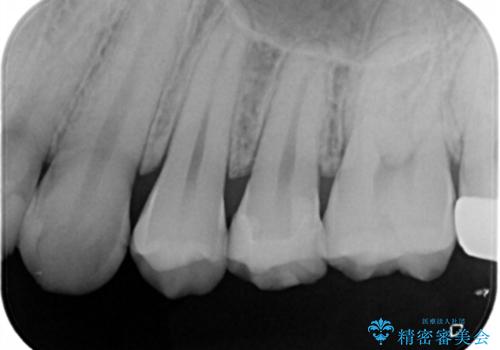

- 左上5番の虫歯治療を主訴に来院された患者様です。

セラミックでの治療を希望されたので形態・切削量を考慮しセラミックインレーでの治療を選択しました。

隣り合っている面(隣接面)は清掃がしづらく虫歯になりやすい場所です。

また、形態の再現が難しいのでインレーなどの補綴物での治療が第一選択となることが多いです。